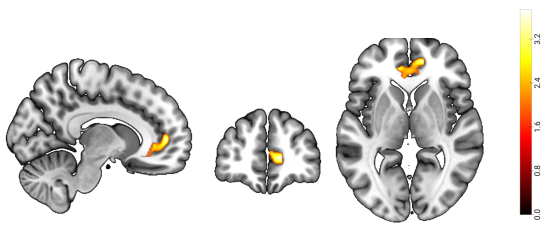

近日,必赢776net必赢776net冯廷勇教授团队在国际著名学术期刊《Behavioral and Brain Functions》(中科院分区SCI一区,IF = 5.1)上发表了名为“The vmPFC-IPL functional connectivity as the neural basis of future self-continuity impacted procrastination: the mediating role of anticipated positive outcomes”的学术论文。该研究基于预期想象的2(指向性:任务过程VS.任务结果)×2(情绪效价:正性VS.负性)模型(Yang & Feng, 2021),采用自由建构范式,收集被试的预期想象想法,并结合基于体素的形态学分析(VBM)和静息态功能连接(RSFC)两种多模态分析方法,深入探究了未来自我连续性影响拖延的神经基础。该研究发现:(1)行为结果表明,未来自我连续性与拖延行为呈负相关关系(见图1);(2)VBM结果发现,未来自我连续性与右侧腹内侧前额叶(right ventromedial prefrontal cortex,RvmPFC)的灰质体积呈正相关关系(见图2);(3)RSFC分析揭示,右侧腹内侧前额叶与左侧顶下小叶(left inferior parietal lobule, LIPL)之间的功能连接(RvmPFC-LIPL)强度与未来自我连续性呈正相关关系(见图3);(4)中介分析发现,预期想象正性结果在未来自我连续性的功能连接(RvmPFC-LIPL)对拖延行为的影响中起到了完全中介的作用(见图4)。基于拖延的时间决策模型(Zhang & Feng, 2020),这些结果说明,未来连续性主要通过预期想象增加正性结果价值,进而减少了拖延行为。本研究从认知神经角度系统地解答了“未来自我连续性通过什么心理过程减少拖延行为”,也为拖延的干预提供了新的视角和理论依据。

图2 未来自我连续性与右侧腹内侧前额叶的灰质体积呈显著正相关